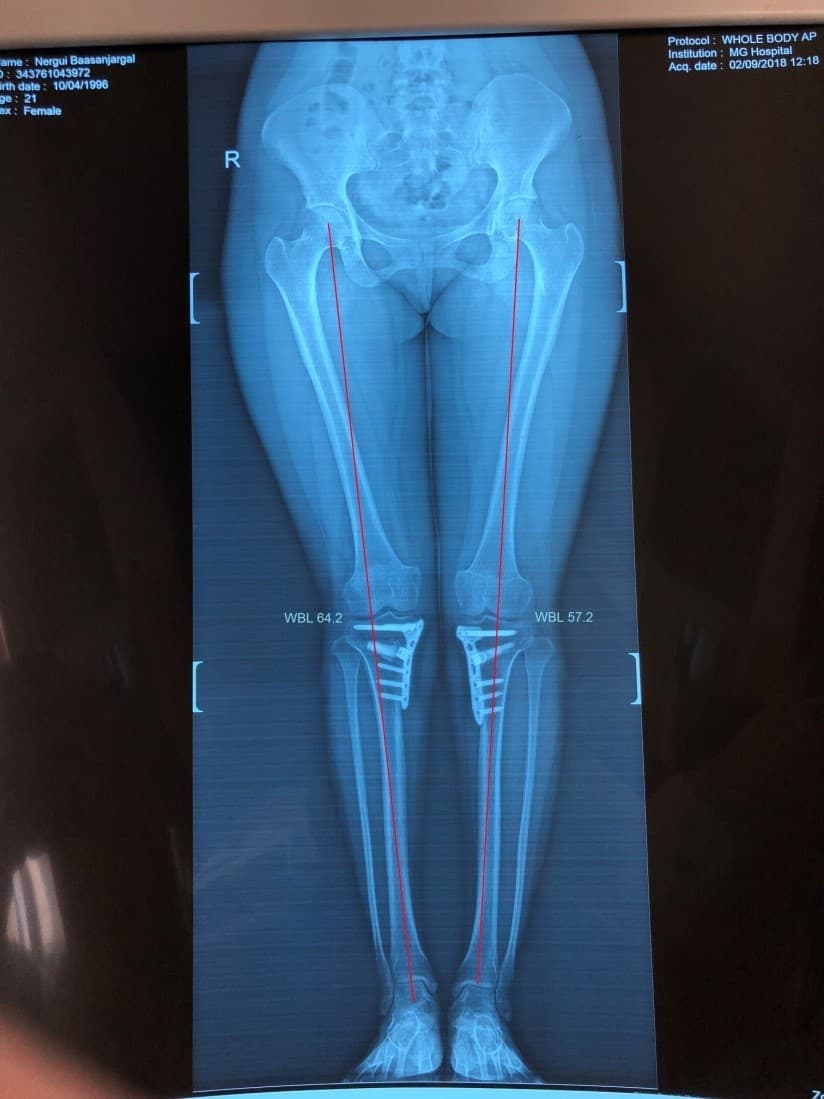

Эмчлүүлэгчийн өвчний явц, үе шат, өвдөгний үений өвдөлтийн хэлбэр, хөдөлгөөний далайц зэргийг сайтар нягталсны үндсэн дээр мэс заслаар биеийн жингийн шугам, шаантны дотор дээд өнцөг, ясны хугарлын цэг, тэлэгдэх өнцгийг нарийн тохируулснаар хүссэн үр дүндээ хүрэх боломжтой.

Шаантны дотор дээд өнцөг мэс заслын өмнө баруун хөлд 84o, зүүн хөлд 82o байсан бол мэс заслын дар аа баруун хөлд 96o, зүүн хөлд 94o болж засагдсан байдал.